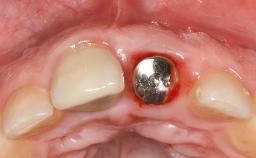

A 79-year-old female patient was referred to the Department of Periodontology of the University of Bern, Switzerland by her private dentist in May 2019. She had been rehabilitated in May 2005 with two tissue-level implants (Institut Straumann AG, Basel Switzerland) at sites 13 and 15, supporting a three-unit cemented fixed dental prosthesis (FDP). The metal-ceramic FDP had been cemented permanently with a glass-ionomer cement (Ketac Cem; 3M ESPE, Seefeld, Germany). Implant 13 had been diagnosed with peri-implant mucositis by the referring dentist in the course of regular supportive therapy. The patient was in good general health, did not smoke, and exhibited good self-performed plaque control.